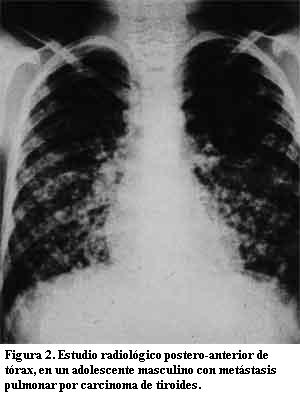

La lesión se localizó en siete (63,64%) a nivel de lóbulo derecho de la glándula tiroides (tabla 2). El patrón histopatológico corresponde en todos los casos examinados a carcinoma papilar, donde tres de ellos presentaron patrón folicular, por biopsia definitiva posterior a tiredectomía, (figura 1); dos (18,18%) de los pacientes cursaban con metástasis pulmonar en el momento del diagnóstico, otros sitios distantes de metástasis no fueron reportados (figura 2). El tipo de intervención realizada fue tiredectomía total en nueve casos y subtotal en dos; ocho pacientes recibieron, además, tratamiento complementario con yodo-131. Sólo un paciente presentó antecedente de radiación como factor de riesgo de importancia relacionado con la entidad. El seguimiento se realizó en 10 pacientes con intervalo de 1 a 13 años y promedio de 4,6 años, con sobrevida de 70%. Tres pacientes fallecieron, entre los cuales se incluyen los dos con metástasis pulmonar, que presentaron evolución clínica desfavorable, falleciendo todos antes de los tres años de seguimiento. Un paciente fue referido para su control a otro centro asistencial por cambio de residencia.